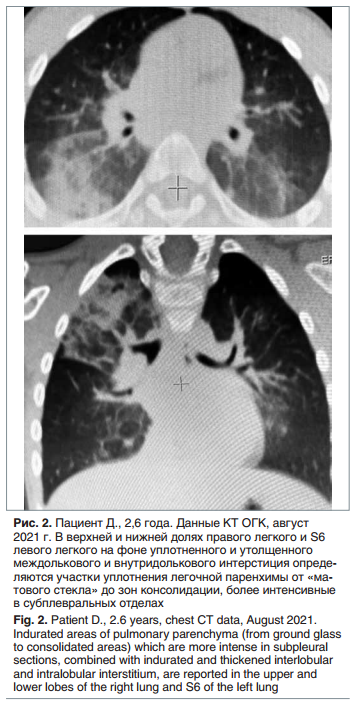

Спустя 3 нед. от последней госпитализации ребенок перенес острый бронхит, вызванный вирусом парагриппа человека 3-го типа (подтвержден лабораторно). Заболевание протекало с фебрильной лихорадкой, одышкой смешанного характера, сильным кашлем. В связи с ухудшением самочувствия пациента, снижением сатурации до 94%, увеличением лабораторной активности (СРБ 25 мг/л), было принято решение об усилении терапии основного заболевания: назначен азитромицин 330 мг/сут в течение 7 дней, а также цефтриаксон 2 г/сут в течение 3 дней. После разрешения бронхита ребенок был выписан домой с рекомендациями продолжить комплексную терапию: иГКС 1000 мкг/сут, ИПВ и азитромицин по схеме (100 мг/сут, 3 раза в неделю) в течение 1 мес. На фоне терапии кашель купировался, подъемов температуры тела больше не отмечалось, самочувствие мальчика улучшилось, одышки не было. На контрольной КТ ОГК через 6 мес. отмечена положительная динамика в виде частичного рассасывания инфильтративных изменений в легких (рис. 2).

На фоне терапии в течение 13 мес. (июль 2021 г. — сентябрь 2022 г.) одышка и кашель купировались, подъемов температуры тела не отмечалось. ОАК, общий анализ мочи, биохимический анализ крови от сентября 2022 г. — без патологических изменений. На КТ ОГК от сентября 2022 г: положительная динамика в виде значительного уменьшения зон консолидации, сохраняется неравномерная воздушность легких, уплотнение легочной ткани по типу «матового стекла». Далее представлена динамика на КТ ОГК за 13 мес. (рис. 3).